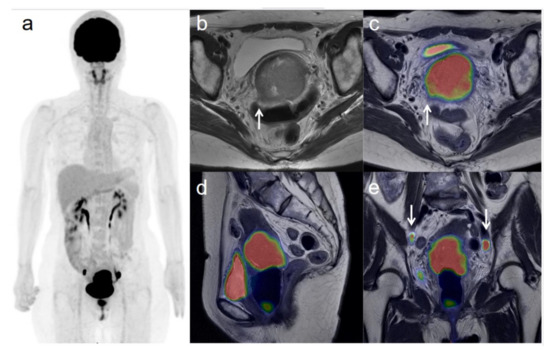

3.3. Revised FIGO Staging

Figure 4. A 75-year-old woman with IIIC2 cervical cancer and paraaortic lymph node metastasis. (a) 18F-FDG PET image FDG uptake by tumor in the cervical cervix (arrow) and pelvic and paraaortic lymph nodes. (b) CT shows paraaortic lymph nodes of short-axis diameter >1 cm (arrows). (c) Axial T2-weighted PET/MR image shows FDG uptake by the paraaortic lymph nodes (arrows). This finding is strongly suggestive of paraaortic lymph node metastasis. After radiotherapy, the size and SUV of the lymph nodes decreased, further suggesting malignancy. (d) Sagittal T2-weighted PET/MR image shows FDG uptake by the cervical tumor. (e) Coronal T2-weighted PET/MR image shows FDG uptake by the cervical tumor and pelvic lymph nodes (arrows).